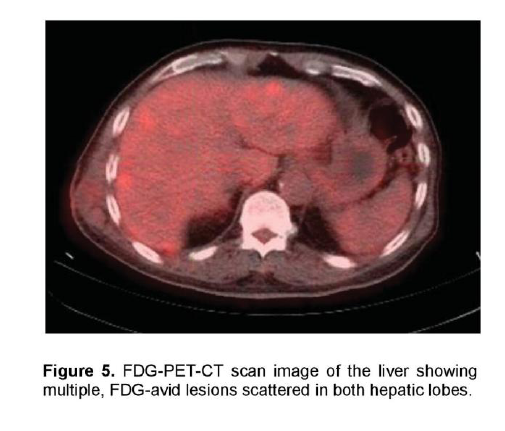

There was a mildly enhancing 1.3 x 1.3 cm mass in the right temporal lobe with FDG uptake similar to that of white matter. The previously seen mediastinal and right hilar lymphadenopathies had intense FDG uptake with standardized uptake value (SUV) up to 7.3 g/ml (Figure 4). In contrast, the previously noted reticular ground glass opacities in both lungs had low-grade uptake on PET. There were multiple hypermetabolic lesions in both hepatic lobes with SUV up to 5.4 g/ml (Figure 5) which appeared normal on the initial CT scan. A 24-hour urinary 5-hydroxyindoleacetic acid (5HIAA) was four times elevated, indicative of tumor secretory activity. He underwent chemotherapy with Carboplatin, Etoposide and Topotecan and radiation therapy with complete disappearance of the brain lesion but with further derangement in liver function.

Figure 5. FDG-PET-CT scan image of the liver showing multiple, FDG-avid lesions scattered in both hepatic lobes.